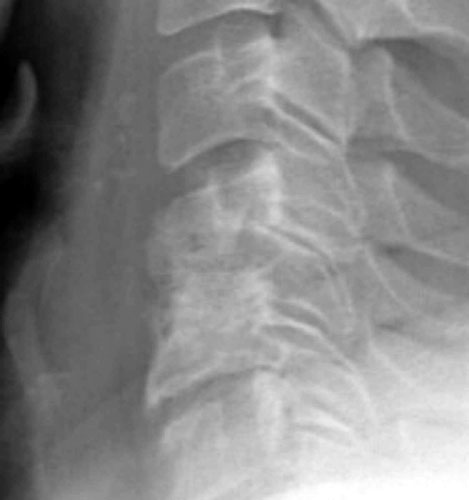

Initial post-operative films show bone graft intact, with mildly

prominent pervertebral soft tissues, as expected in the immediate post-operative

period. |